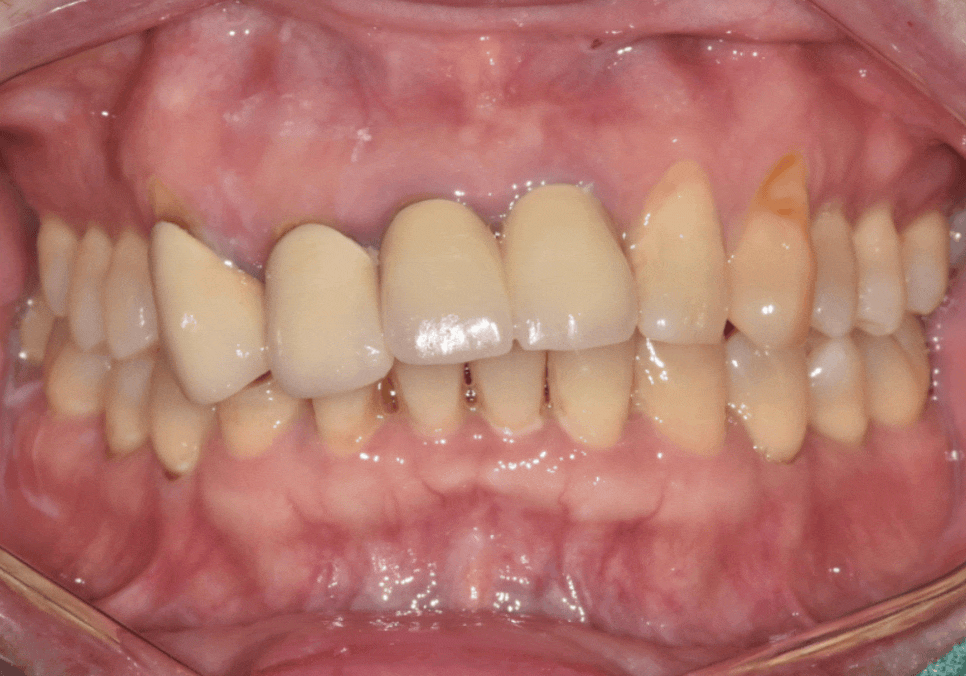

이 환자분은

오래전 위 앞니 4개를

보철로 씌우셨는데,

시간이 흐르면서

심미적으로나 기능적으로

문제가 생긴 상태였습니다.

입안을 자세히 살펴보니

원인은 크게 세 가지였습니다.

유독 길게 제작된 위 앞니가

아랫니를 계속 건드리면서,

아랫니 속살(상아질)이 비칠 만큼

심하게 마모되어 있었습니다.

아랫니가 닳아 키가 작아지다 보니,

상대적으로 윗니는 더 들쑥날쑥하고

삐뚤어 보일 수밖에 없었죠.

잇몸이 내려가면서

뿌리가 드러나보이고,

보철 안쪽의 금속 테두리가

까맣게 보였습니다.

삐뚤어보였던 치아 라인이

보철 치료를 통해

눈에 띄게 개선되었습니다.

특히 구강스캐너와 원내기공소의

디지털 시스템 덕분에,

더욱 신속하면서도

정교한 보철물을 완성할 수 있었습니다.